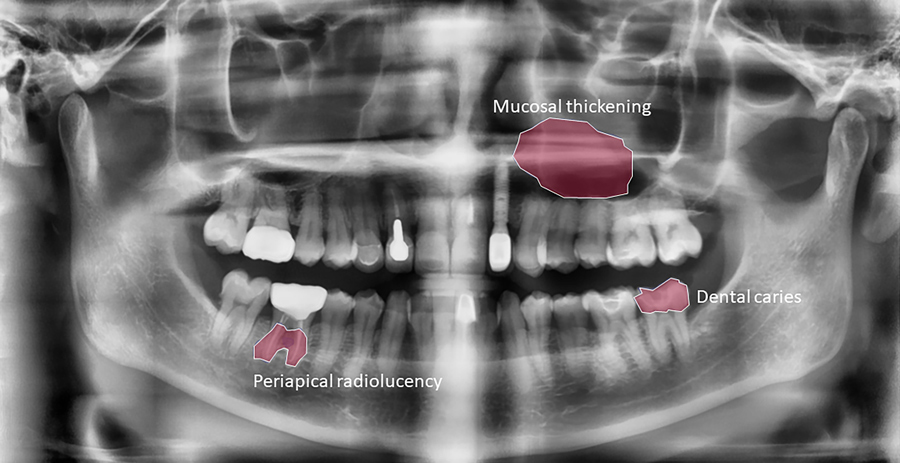

研究人员描述这些主要的牙异常会如何影响病人口腔健康及其生活质量置之不理可产生严重后果,特别是当它们与系统性疾病相关联时。早期检测可预防严重结果并为其他系统性疾病提供标志17个异常点根据其临床特征和位置划分为四类:恶意损伤、计算学、牙区异常点和周边地区异常点

形形色色分解或牙口洞是牙科最常见问题它们的预防和早期诊断至关重要,因为它们若被忽视可引起更严重的问题。团队分四组精细诊断,以利及早检测,防止进退和牙组织退化

Calcification描述加积和口香糖全景牙线报上很少出现它,但检测对防止任何进一步进展至关重要

牙类异常区包括牙病特征和异常牙型可引起症状,包括出血、疼痛和大通病研究者选择包括六大牙异常对牙健康至关重要外部根吸附、受撞击牙、近似放射性(辐射变换常因炎症)、残留根和超数牙还可以视之为诊断标志和解剖因素,为病人未来牙工提供参考举例说,全景牙图片可用来评价提取前神经损伤风险

位于牙区以外周边地区的异常点很少与口腔健康相关联。表示发炎过程并可作为诊断其他相关疾病的标志举个例子,薄膜薄膜厚度可指向条件,如支持牙的骨骼中发生的动脉周期性炎(牙下组织皮炎)和动脉骨损